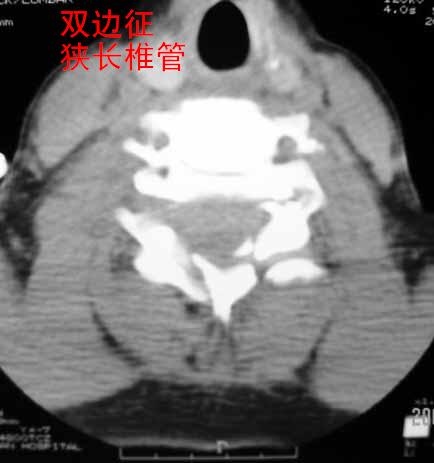

以下是引用zhangzhongshou在2007-4-29 22:53:00的发言:[br]1、c5半脱位,i度前滑脱。[br]2、c5椎板骨折。[br]3、第7幅图像显示右侧椎板骨折,哪一节颈椎,楼主自己知道。[br]4、c2、3附件融合畸形。[br]5、考虑环椎后桥,亦为正常变异。